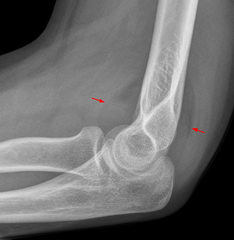

DescriptionFettpolsterzeichen pathologisch Ellenbogen.png English: Fat pad sign: Ventral fat pad bowed and dorsal fat pat visible. The fracture of radius head is not visible directly. Deutsch: Pathologisches Fettpolsterzeichen bei einer okkulten Radiusköpfchenfraktur. Das ventrale Fettpolster ist bogig nach vorne verlagert, das dorsale Fettpolster ist sichtbar. Date Source: Hellerhoff This file is licensed under the Creative Commons Attribution-Share Alike 3.0 Unported license.

| current | 18:29, 15 January 2015 | ![]() | 1,024 × 1,050 (683 KB) | Rossdonaldson1 (Talk | contribs) | DescriptionFettpolsterzeichen pathologisch Ellenbogen.png English: Fat pad sign: Ventral fat pad bowed and dorsal fat pat visible. The fracture of radius head is not visible directly. Deutsch: Pathologisches Fettpolsterzeichen bei einer okkulten Radiuskö |